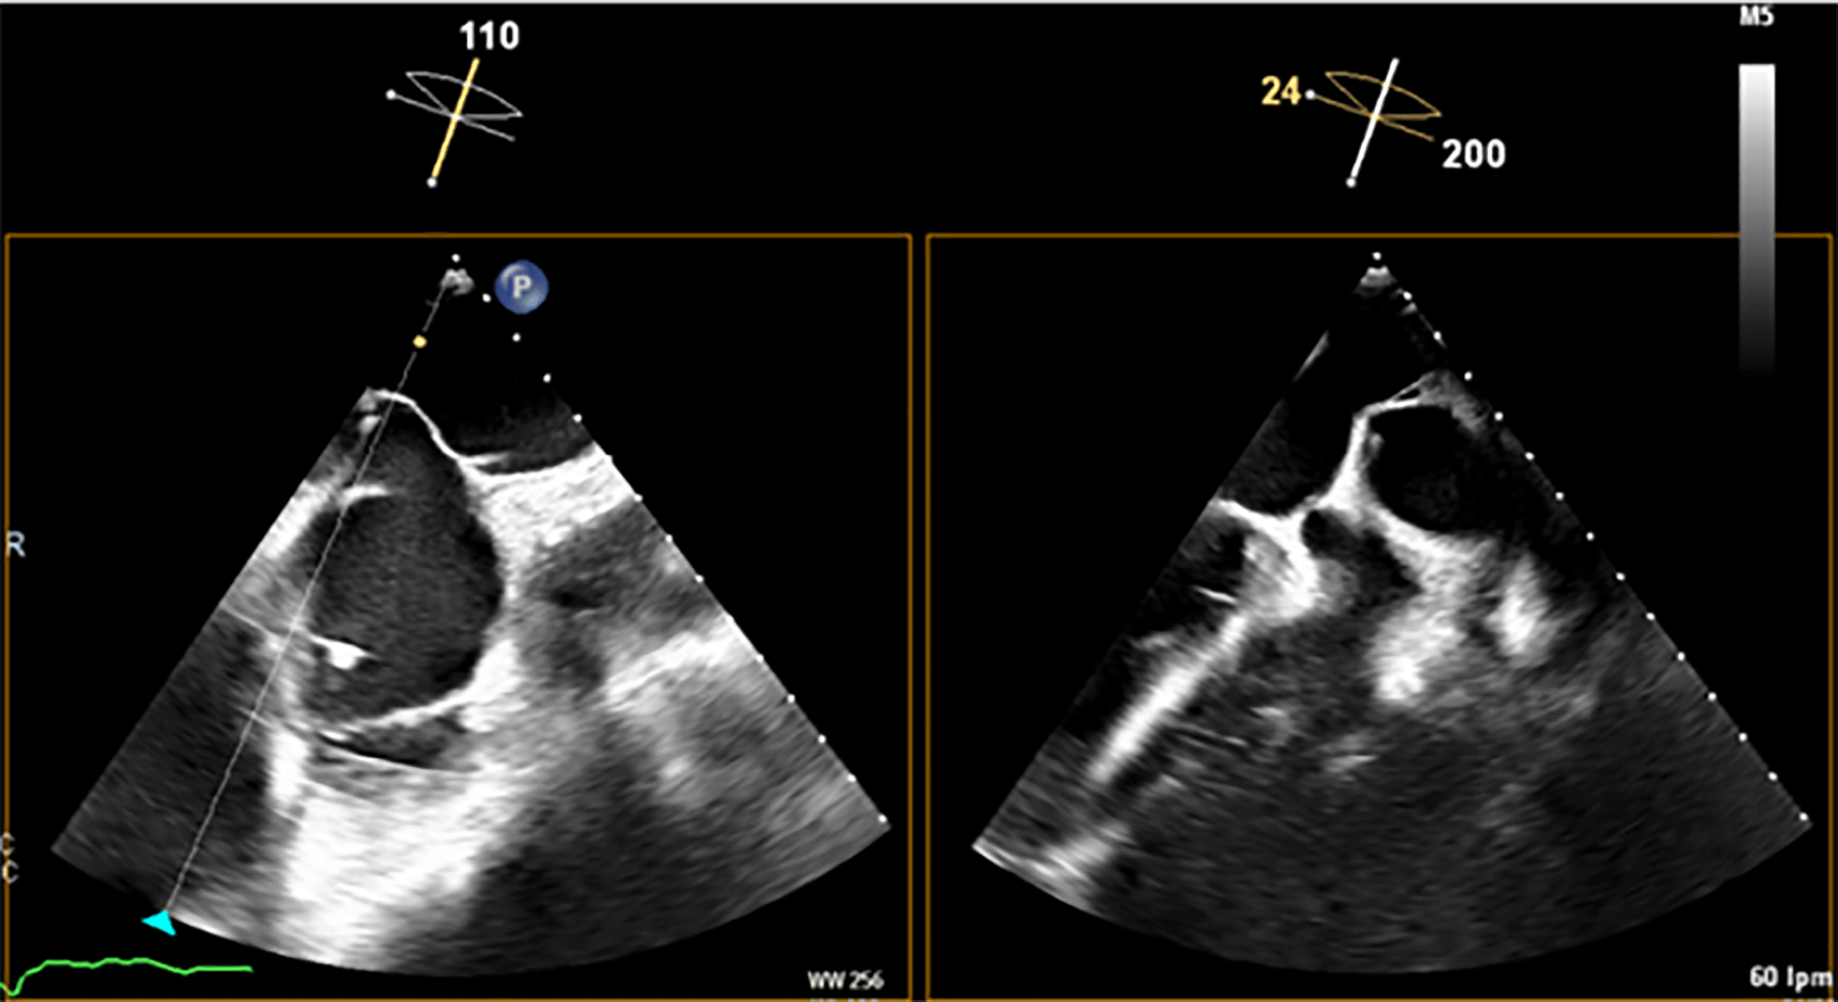

Fig. 6.

Middle and inferior transseptal puncture (TSP) approach. A transseptal puncture (TSP) in the inferior (A) and middle (B) portions of the fossa ovalis in a patient with an inverse chicken-wing morphology (C) of the left atrial appendage (LAA), clearly visualized in the angiographic image (D).